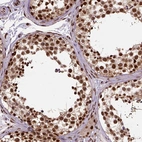

Immunohistochemical staining of human cerebral cortex, duodenum, skin and testis using Anti-NACC1 antibody HPA021238 (A) shows similar protein distribution across tissues to independent antibody HPA062245 (B).